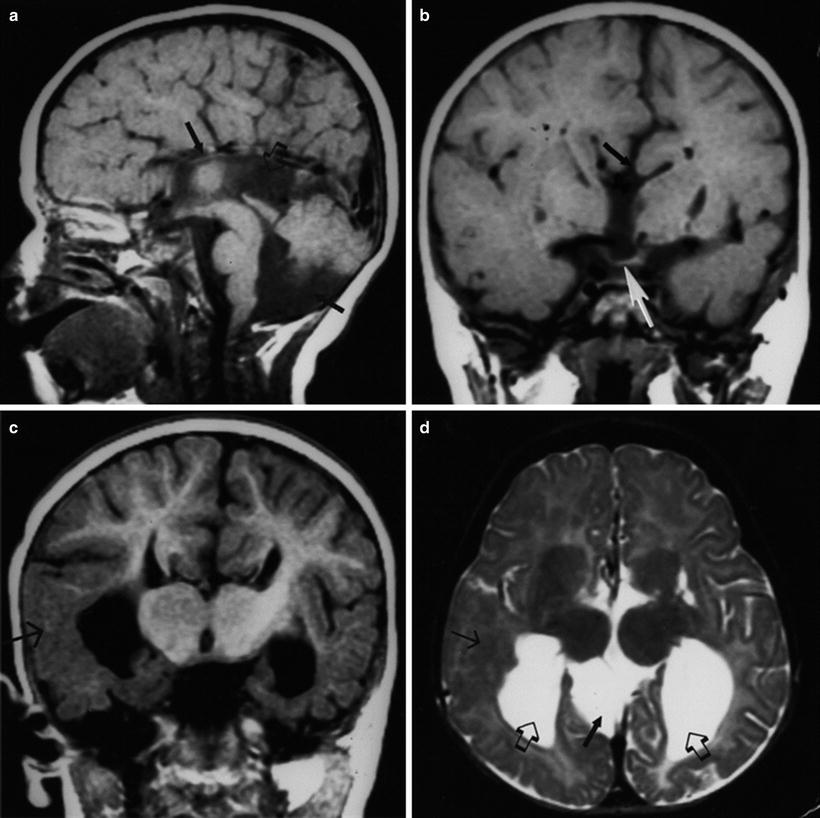

Neurohypophyseal Abnormalities

Posterior pituitary ectopia. (a) T1-weighted sagittal MR image demonstrating normal hyperintense signal of posterior pituitary gland (lower white arrow), normal pituitary infundibulum (lower white arrow), optic chiasm (upper white arrow). Open arrow denotes normal corpus callosum. (b) T1-weighted sagittal MR image demonstrating posterior pituitary ectopia (upper white arrow), which appears as abnormal focal area of increased signal intensity at tuber cinereum. Note absence of pituitary infundibulum and absence of normal posterior pituitary bright spot (lower white arrow). Upper white arrow denotes ectopic posterior pituitary gland. This child had a normal septum pellucidum and corpus callosum. Used with permission, from Brodsky and Glasier [58]. Copyright 1993, American Medical Association.

The finding of an absent pituitary infundibulum with no orthotopic or heterotopic bright spot corresponding to the posterior pituitary gland (Fig. 11.42) signifies loss of antidiuretic hormone secretion, which is associated with diabetes insipidus. When this finding is present, the anterior pituitary hormones are deficient as well.